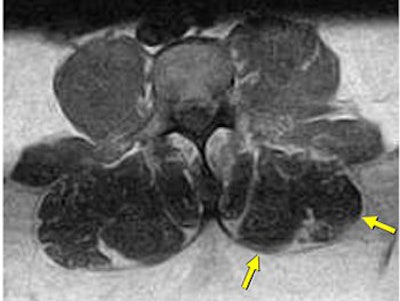

![]() |

| Same patient as above. Left lateral paraspinal muscle asymmetry indicating deconditioning. Axial-loaded images were obtained with the Portal Gravity System. |